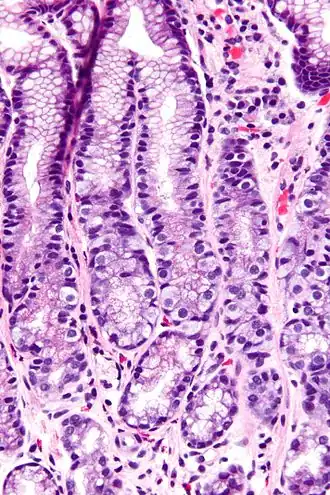

G-cellen hebben een kenmerkend microscopisch uiterlijk waardoor ze te onderscheiden zijn van andere cellen in het antrum van de maag; hun celkernen bevinden zich centraal in de cel. Ze bevinden zich in het middelste deel van de maagklieren.